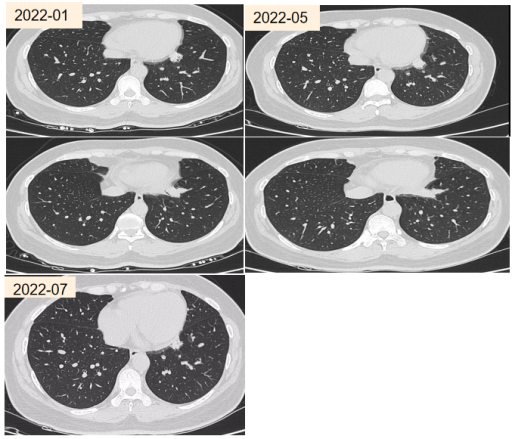

患者,女性,33岁,主因“反复咳嗽、胸闷7年,发现肺部病变3月”于2022年4月第二次入院。既往激发试验阳性,诊断为支气管哮喘,自诉“咳果冻样痰”,查白细胞计数8.74×109/L,嗜酸性粒细胞比值5.9%(↑),绝对值0.5×109/L。lgE 593.95 IU/ml。外送烟曲霉特异性IgE阴性,烟曲霉IgG阴性。

气管镜:左内前基底段条状分泌物。影像学可见指套状物。

abp在医学是什么意思王凌伟教授:2021日本ABPA/ABPM诊断标准解读_https://www.jmylbn.com_新闻资讯_第16张

abp在医学是什么意思王凌伟教授:2021日本ABPA/ABPM诊断标准解读_https://www.jmylbn.com_新闻资讯_第17张

患者无鼻窦炎、无支气管扩张、无曲霉致敏证据。但符合日本ABPM诊断标准。患者按照ABPM治疗,复查胸部CT有吸收,目前仍在随访中。